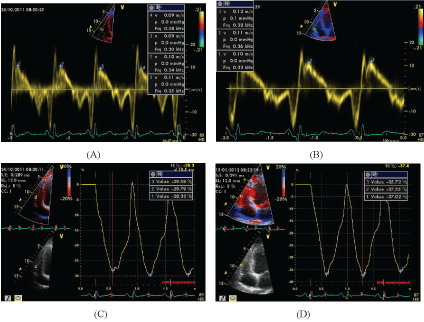

Subjects in both groups were evaluated at baseline and three months after the initiation of the intervention. Assessments included measuring the serum level of hsCRP and transthoracic echocardiography. Echocardiography was performed for both groups using a Vivid 7 Dimension ultrasound scanner (GE Vingmed, Horten, Norway) with a 4-MHz transducer S' wave of the tricuspid annulus, and the longitudinal systolic strain in the base and mid segment of the RV free wall were used to assess RV systolic function (Figure 2). In addition, the E wave velocity of the tricuspid inflow, E' peak velocity in the lateral annulus of the tricuspid valve, and E/E' were measured as echocardiographic parameters to evaluate RV diastolic function. The PAP was calculated through the tricuspid regurgitation peak pressure gradient. Global left ventricular longitudinal strain (GLS) was assessed with the automated functional imaging (AFI) method using three apical views (apical long-axis, 4- and 2- chamber views) in the grayscale. The RV and right atrium (RA) size and left ventricular ejection fraction (LVEF) were also measured.

Figure 2: Echocardiographic Assessment of right ventricle function using Sm (A,B) and Longitudinal Strain in RV free wall (C,D) which was done before (A,C) and three months after Atorvastatin Therapy (B,D). Note the improvement in Sm and RV strain in this case.